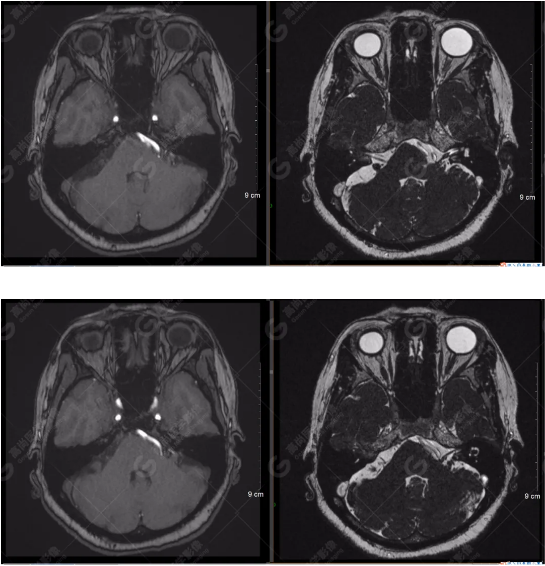

雙側(cè)大腦半球?qū)ΨQ,灰白質(zhì)對比正常,右側(cè)顳部見一囊狀長T1長T2信號影,F(xiàn)LAIR序列呈低信號;余腦實質(zhì)內(nèi)未見局灶性信號異常。各腦室、腦池大小、形態(tài)均正常,中線結(jié)構(gòu)居中,幕下小腦、腦干無異常。矢狀面示垂體大小形態(tài)正常,未見局灶性信號異常。

顱腦MRA及ciss序列示腦基底動脈環(huán)完整,雙側(cè)頸內(nèi)動脈末段、大腦前動脈、大腦中動脈、大腦后動脈及其主要分支顯影良好,管徑及走行正常,無明顯局灶性增粗或變細(xì)。雙側(cè)椎動脈末段沿延髓左側(cè)向上走行,左側(cè)面聽神經(jīng)輕度受壓移位,左側(cè)面聽神經(jīng)周圍見細(xì)小血管包繞。右側(cè)面聽神經(jīng)及雙側(cè)三叉神經(jīng)周圍未見異常血管影。

1.雙側(cè)椎動脈末段沿延髓左側(cè)向上走行,左側(cè)面聽神經(jīng)輕度受壓移位,左側(cè)面聽神經(jīng)周圍見細(xì)小血管包繞,可符合面聽神經(jīng)壓迫綜合征。

2.右側(cè)顳部蛛網(wǎng)膜囊腫。